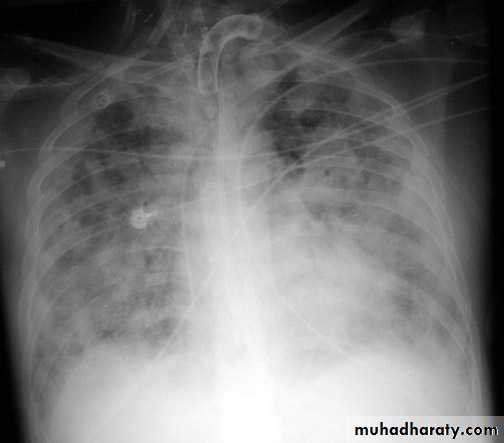

• Complications of chest injuries 1-ARDS: Syndrome of acute RF with the formation of a non –cardiogenic pulmonary edema leading to reduced lung compliance and hypoxaemia which is refractory to oxygen therapy characterized by bilateral diffuse pulmonary infiltrate on chest X-ray (white lung) .A less severe case (ALI=acute lung injury ) which consists of a non specific pathological changes in the lung in response to a specific insult . 2-Atelectasis3-Infection4-Pulmonary embolism5-Air embolism6-Traecheal complications7-Cardiac arrhythmias